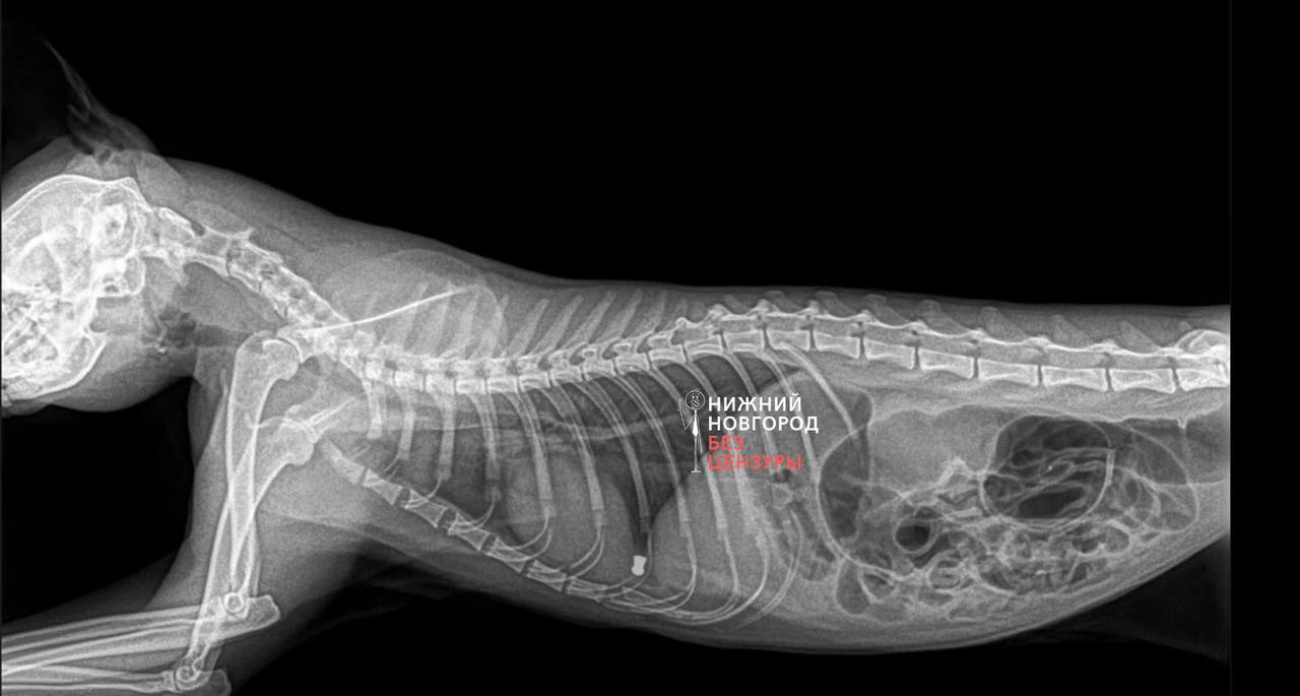

По словам местных жителей, один кот получил пулю в лапу, у другого обнаружили металлический предмет в животе, потребовалась срочная операция. Жители отмечают, что подобные случаи происходят не впервые. По их словам, жалоб на стрельбу по животным становится все больше, и пострадавших котов уже несколько.